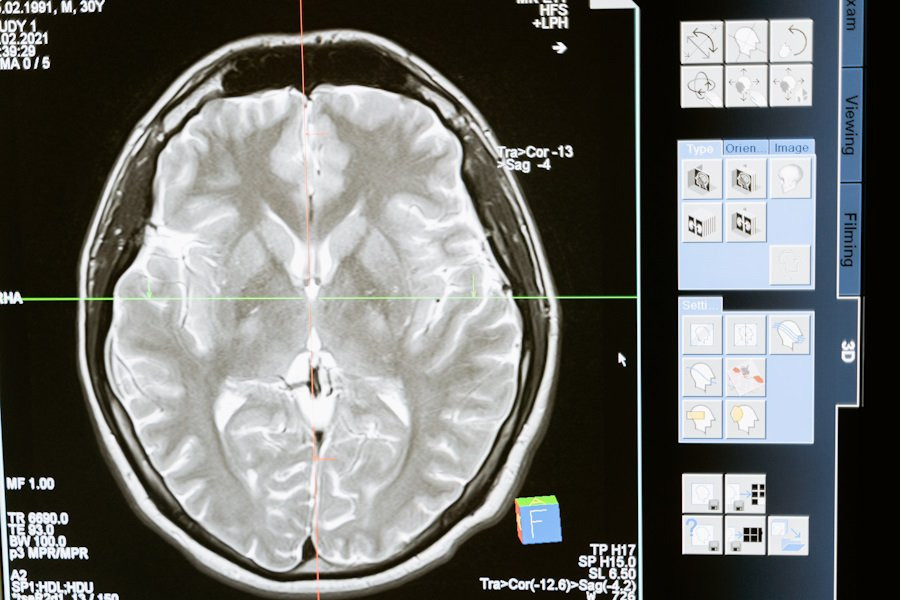

Ученые сделали важный шаг в понимании того, как мозг интегрирует информацию во время сложных когнитивных процессов, таких как чтение. В новом исследовании, проведенном в University of California, было обнаружено, что нейроны в различных областях мозга синхронизируются, когда человек читает и принимает семантические решения.

Результаты этого исследования опубликованы на портале Nature. Исследователи использовали внутричерепную электроэнцефалографию (ЭЭГ) для наблюдения за активностью мозга у участников эксперимента.